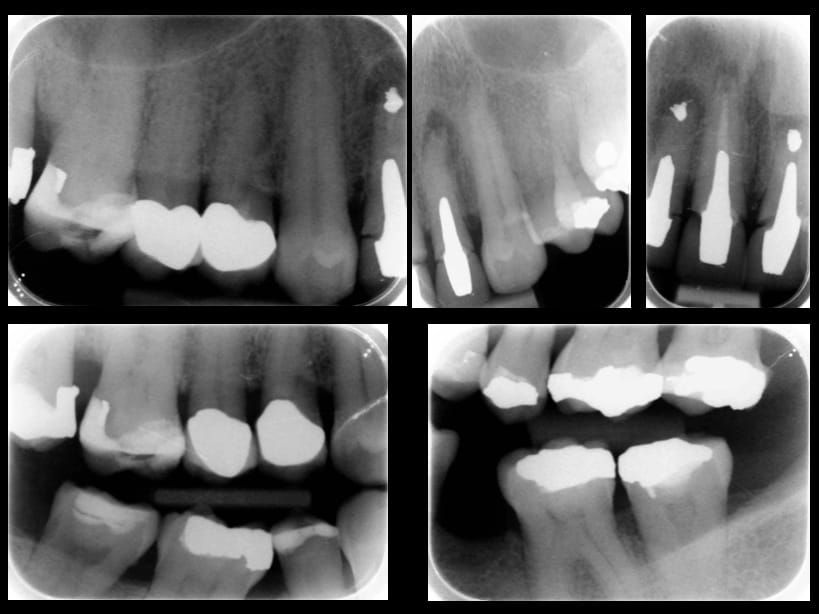

- Extract the upper 2-2 teeth and replace with an interim acrylic based partial denture. Reline the interim denture over 9 - 12 months, replacing with a definitive cobalt chromium based partial denture. The definitive denture would ideally be designed as an occlusal protective splint to reduce the the potential for mechanical wear and breakages of the moderately/heavily restored maxillary dentition. In addition, should further upper teeth require extraction they could be added on to the denture cobalt chromium framework - therefore a new prosthesis would not be required as future teeth are lost. This option would produce an excellent aesthetic outcome. This is the option the patient chose to have.

Following consultation and second discussion appointment the patient chose to have option 3 namely, a maxillary cobalt chromium based partial denture/protective occlusal splint. The clinical situation and treatment process is shown in detail below with photographs. The patient was successfully rehabilitated with this and her quality of life considerably improved. The clinical work was provided by Finlay and the technical work by Rowan.